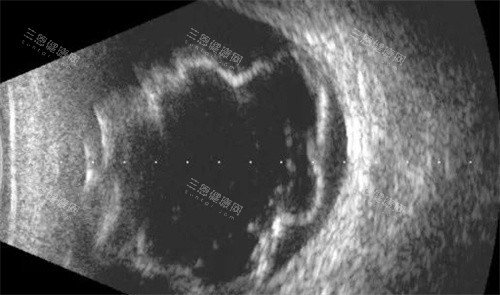

当前人工视网膜研发形成两大主流方向,均已完成关键技术验证,为2030年临床准入奠定基础。电极刺激路线中,PRIMA系统的表现非常有代表性,其2×2mm的柔性无线植入片包含378个光伏像素,可直接替代坏死的感光细胞完成光电转换。

该系统通过专用眼镜捕捉影像,经近红外光投射至植入物产生电脉冲,促活残余视网膜神经元,在欧洲17个中心的试验中,32名受试者里26人实现视力的临床显著改善,部分可完成阅读与方向辨别。